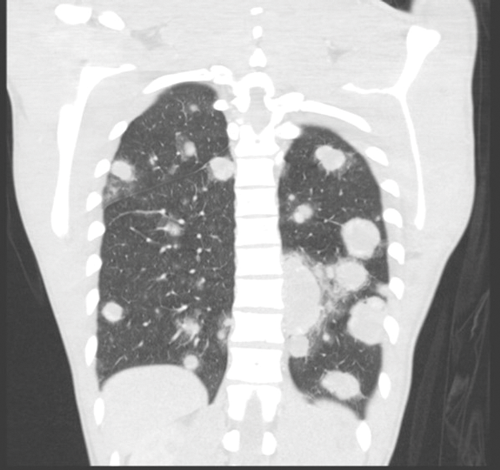

Figure 7. Bilateral lung metastases seen on coronal CT.

Stage three is where there is spread to distant nodes or other organs, most commonly the lungs and the liver (Figure 7).

Brain imaging is advised if there are over 20 lung metastases, HCG is >10,000 or there is focal neurology. The brain metastases are often haemorrhagic so are high attenuation on pre-contrast CT [4].